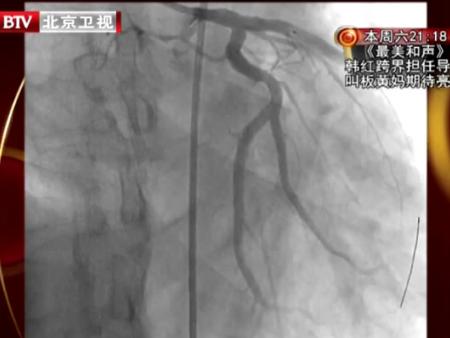

專家建議,一旦心絞痛發(fā)作頻率加劇了,我們可以通過做平板運動試驗來監(jiān)測心肌缺血的程度,或者通過做冠脈CT或冠脈造影來確定血管的狹窄程度,出現(xiàn)問題及時解決就可以避免心梗的突發(fā)了。這種簡單的平板運動試驗還可以幫助已經(jīng)確診冠心病的患者,通過運動試驗找到運動量的上限來避免日?;顒訉τ谛慕g痛的誘發(fā),以達到更好維護心臟功能的目的。更多內(nèi)容請收看本期節(jié)目。